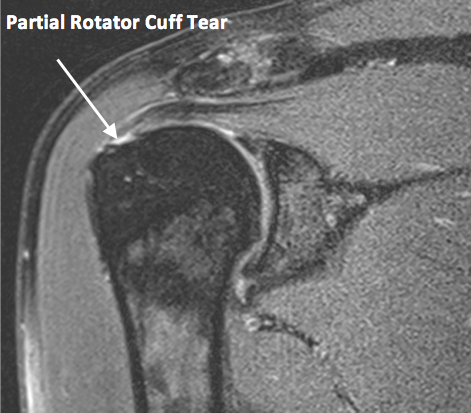

회전 근개(힘줄) 파열의 MRI

MRA (Magnetic Resonance Arthrography)입니다

그 방법은 어께 관절 부분에 염색약을 주사한 후, MRI 촬영을 하면

어께 회전 근개 파열이 있는 곳으로 염색약이 새어 나가서

어께 관절의 정확한 이상 부위를 쉽게 알 수 있도록 하는 것입니다

위의 그림에서 하얗게 보이는 부분이 염색약 입니다